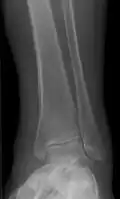

Periosteal reaction from venous stasis